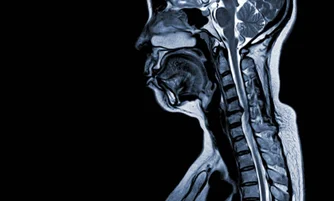

Cervical Spondylosis Specialist

A spine doctor who diagnoses and treats age-related degeneration of the cervical spine causing neck pain and nerve compression.